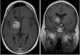

Enhancing sellar lesion